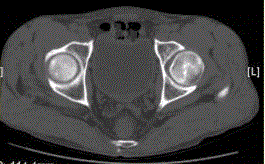

问题 患者男,47岁,左髋部疼痛及压痛6个月,“4”字试验阳性。左髋关节内、外旋活动受限。检查提示:左髋关节活动轻度受限,大腿上部轻压痛。血常规检查正常。髋关节CT及MRI如下图。 根据髋关节CT和MR影像,你认为此病例的影像学表现有

选项 A.CT检查未见异常 B.左侧股骨头内可见线样高密度影 C.左股骨头塌陷变扁,其内可见条带状硬化 D.左股骨头内见蜿蜒走行的T1、T2低信号条带影 E.左髋关节腔内可见弧线状长T1、长T2信号 F.左髋关节间隙变窄

答案 BDE